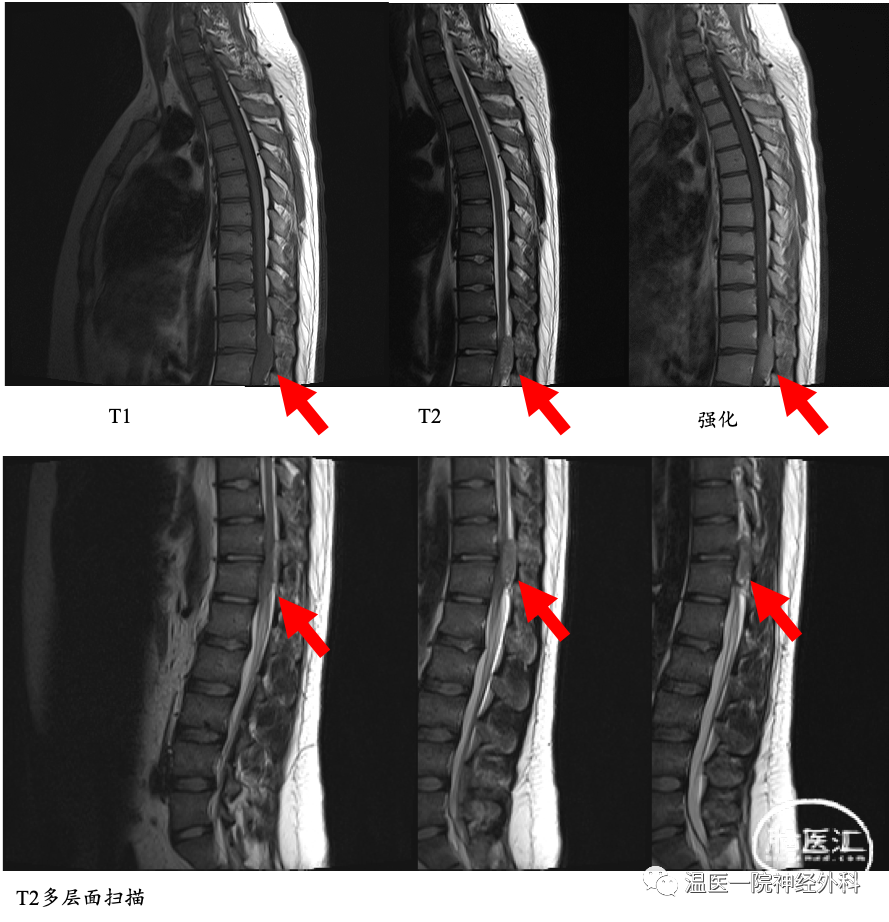

患者,男,22岁,因“腰背部疼痛20余天,双下肢乏力5天”入院。

患者20余天前出现腰背部疼痛,针扎样,卧位明显,逐渐累及双大腿前外侧,遂至浙江省某医院就诊,予止痛等对症治疗后疼痛有所缓解,5天前患者出现双下肢乏力,左下肢为著,无法行走,伴双下肢麻木感,至我院急诊就诊,以“吉兰-巴雷综合征?”收住神经内科,查胸椎MRI示“T11-12平面椎管内占位”,为进一步手术治疗,拟诊“椎管内占位”转入我科。